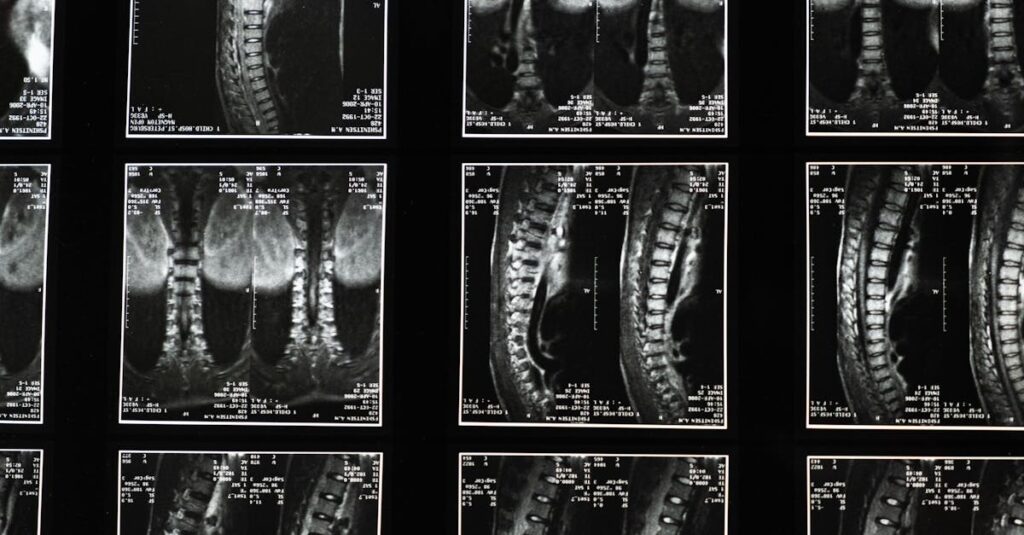

La sciatique est liée à la compression ou à l’irritation du nerf sciatique. Les symptômes peuvent inclure une douleur intense dans le bas du dos et une sensation de picotement dans une jambe. En raison de ces symptômes, il est crucial que le patient partage des détails précis avec son thérapeute. Une description complète des symptômes aide le professionnel à poser un diagnostic approprié.